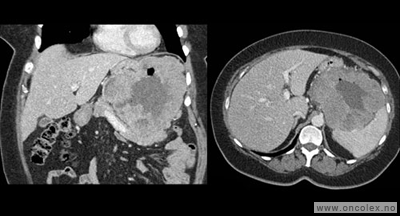

• CT toraks, buk og bekken er standard utredningsmetode ved svulst i buken og på bakre bukvegg, og kan gjøres ved lokalsykehus. De viktigste fordelene ved CT er at undersøkelsen tar kort tid. Innføringen av spiral-CT, og spesielt multislice-teknikk, har forbedret kvaliteten. Røntgen av lungene er som regel tilstrekkelig for å oppdage eller utelukke spredning til lunge.

• MR. Selv om CT foretrekkes når det gjelder buk og bekken, er MR ypperlig tilleggsundersøkelse for å vurdere svulster i bekkenet. Mens pasientens bevegelser reduserer bildekvaliteten av buken og til en viss grad bakre bukvegg, kan MR av bekken være til stor hjelp for å definere omfanget av sykdommen og for å fastsette riktig diagnose i bekkenet.

Typiske funn

Bildeeksempler